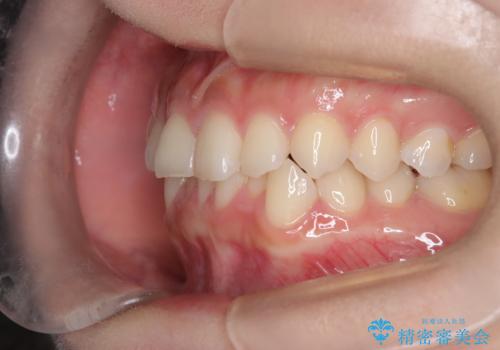

- 前歯のガタガタが気になるとのことでご相談いただきました。診察すると、歯列のスペースが不足し、前歯が重なっている状態でした。抜歯をせずに整えるため、歯と歯の間をわずかに削るIPR(歯列幅径削除)と、奥歯を後方へ動かす遠心移動を組み合わせてスペースを確保しながら並べる治療計画を立てました。

インビザラインを用いて歯を少しずつ移動させながら、IPRで微調整を行い、スペースを確保しました。また、奥歯を遠心移動させることで、前歯を自然な位置に並べることができました。治療後は、「ガタガタがなくなり、スムーズな歯並びになった」と患者様にもご満足いただきました。